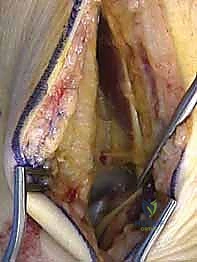

المرحلة الثانية: النهج الجراحي (الشقوق الجراحية)

نظراً لتعقيد عظم الكاحل، غالباً ما يتطلب الأمر شقين جراحيين (Dual Approaches) للوصول إلى العظم من زوايا مختلفة دون تدمير الأنسجة السليمة:

* النهج الأمامي الإنسي (Anteromedial Approach): شق يتم إجراؤه على الجانب الداخلي للكاحل، بين وتر العضلة الظنبوبية الأمامية والكعب الإنسي. يتيح هذا الشق رؤية ممتازة لعنق الكاحل والجانب الداخلي لجسم العظم. في بعض الحالات المعقدة، قد يضطر الدكتور هطيف لإجراء "قطع عظمي للكعب الإنسي" (Medial Malleolar Osteotomy) للوصول إلى عمق المفصل، ثم إعادة تثبيته لاحقاً.

* النهج الأمامي الجانبي (Anterolateral Approach): شق يتم إجراؤه على الجانب الخارجي، يتيح رؤية النتوء الجانبي، المفصل تحت الكاحلي، والجانب الخارجي للعنق والجسم.

المرحلة الثالثة: التنظيف والرد (Reduction)

بعد كشف العظم المكسور، يقوم الدكتور هطيف بحذر شديد بتنظيف منطقة الكسر من التجلطات الدموية، والأنسجة المتمزقة، وشظايا العظام الصغيرة التي قد تعيق التئام الكسر.

هنا تبدأ المرحلة الأهم: "الرد". باستخدام أدوات دقيقة، يتم إعادة القطع العظمية المكسورة إلى مكانها التشريحي الأصلي بدقة مليمترية. يتم تثبيت القطع مؤقتاً باستخدام أسلاك كيرشنر (K-wires) الدقيقة.